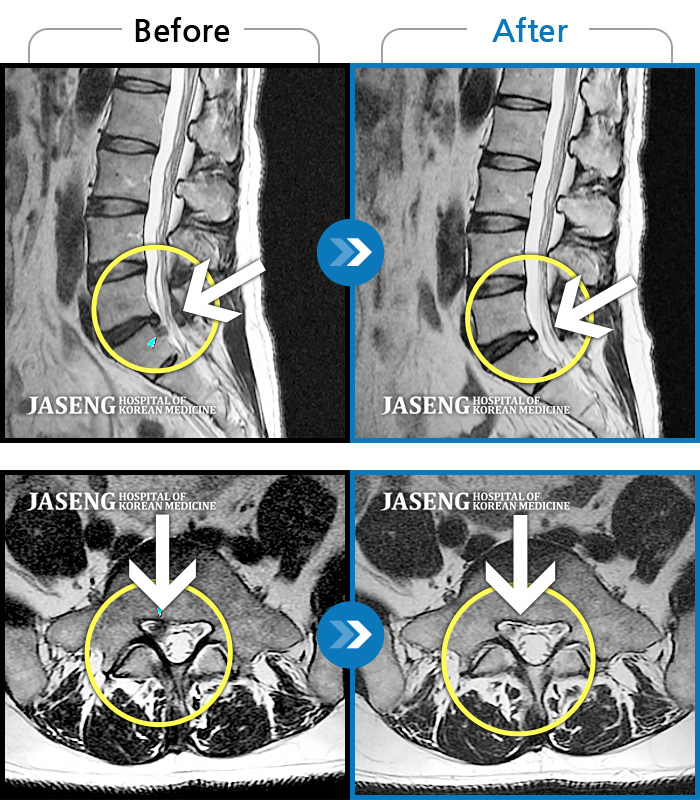

허리디스크

보라매 · 신원준 원장

허리통증과 우측 다리 저림이 심해서 앉거나 서기도 힘들어요

촬영시기

2023.08.01 ~ 2023.11.18

2023.12.08